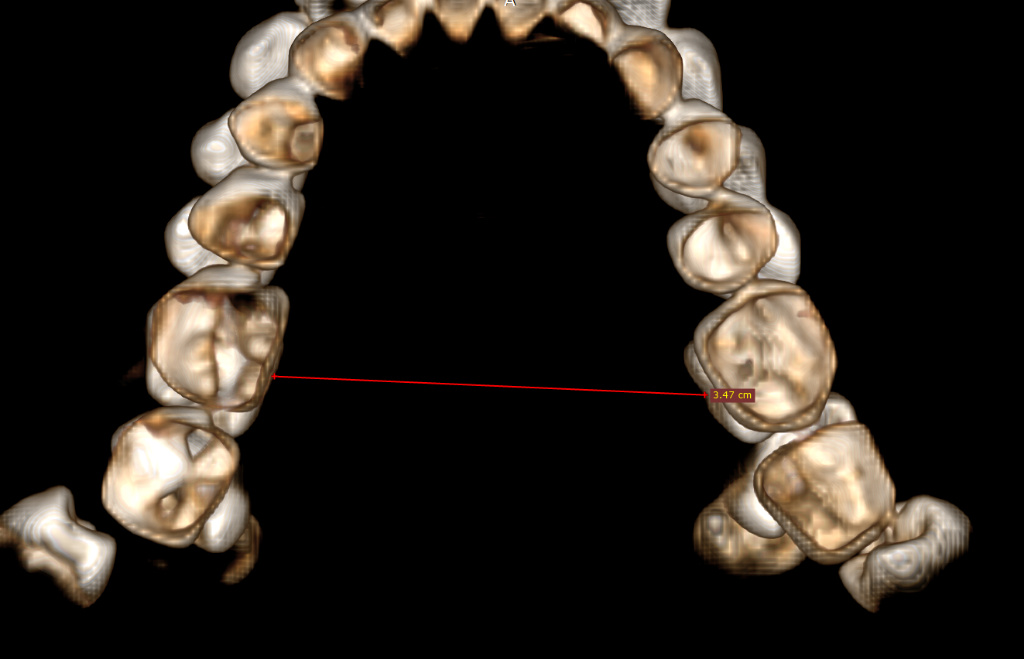

CBCT (Front + Side) + OPG (Old Before & New After braces) (need decompensation)

Disclaimer: I’ve done some preliminary measurements on my CBCT using RadiAnt and Romexis. I’m not a pro, so if I messed up some calculations, please let me know. These should be roughly accurate though.

My Analysis (Based on CBCT):

- Inter-molar Width: ~34.7mm (Narrow palate, teeth in compensation).

- Skeletal Expansion (MARPE/MSE/FME/SARPE): My inter-molar width is ~34.7mm. I’m debating and honestly I don't have much knowledge about this. I want to maximize midface widening and cheekbone support. Given I'm planning Bimax anyway, which one would you guys suggest?